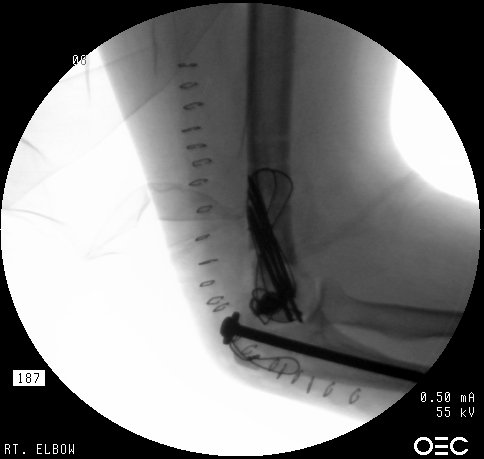

Clinical Example: Comminuted transcondylar distal humerus fracture

An example of a difficult management problem. This patient is a mid 60s year old woman who sustained multiple injuries in a motor vehicle accident, including bilateral calcaneal fractures and a closed distal humerus fracture. She was initially treated in another city.

Initial injury:

Films on arrival, one week after surgery. Neurovascular exam is normal. Early loss of fixation.